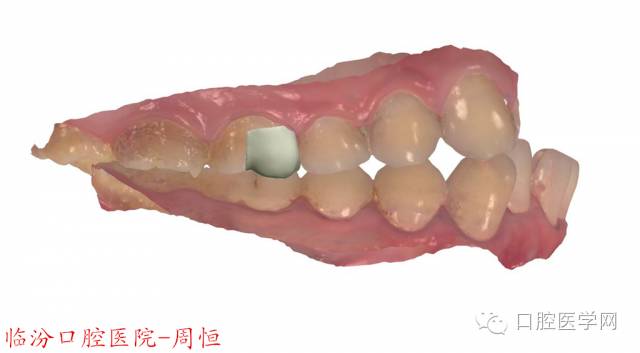

圖5 3D掃描咬頜觀

圖6 3D掃描頜面觀

圖7 3D掃描頜面觀